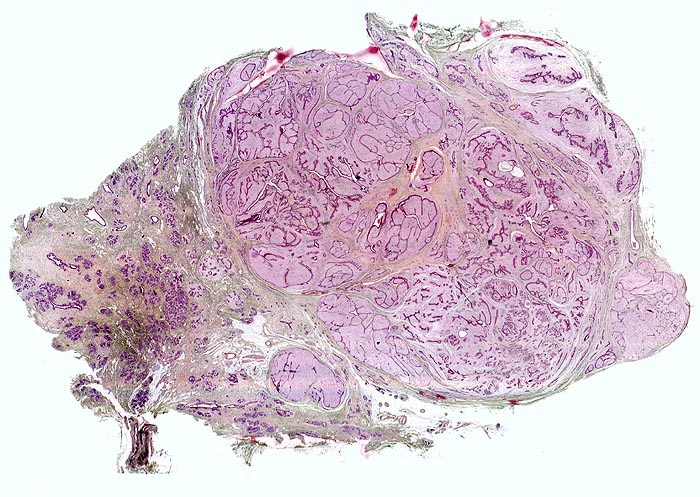

Makroskopisch haben die runden knolligen weissen Tumoren eine mittlere Grösse von 1-2cm. In 15% der Fälle finden sich multiple Fibroadenome. Auf Schnitt sind die komprimierten Gänge als spaltförmige Zeichnung erkennbar.

Morphologische Merkmale:

• Zwei scharf begrenzte Tumorknoten.

• Biphasischer organoid aufgebauter Tumor bestehend aus kompaktem zellarmem fibroblastärem Stroma, das in konzentrischen Lamellen um verzweigte, miteinander anastomosierende Drüsenschläuche angeordnet ist.